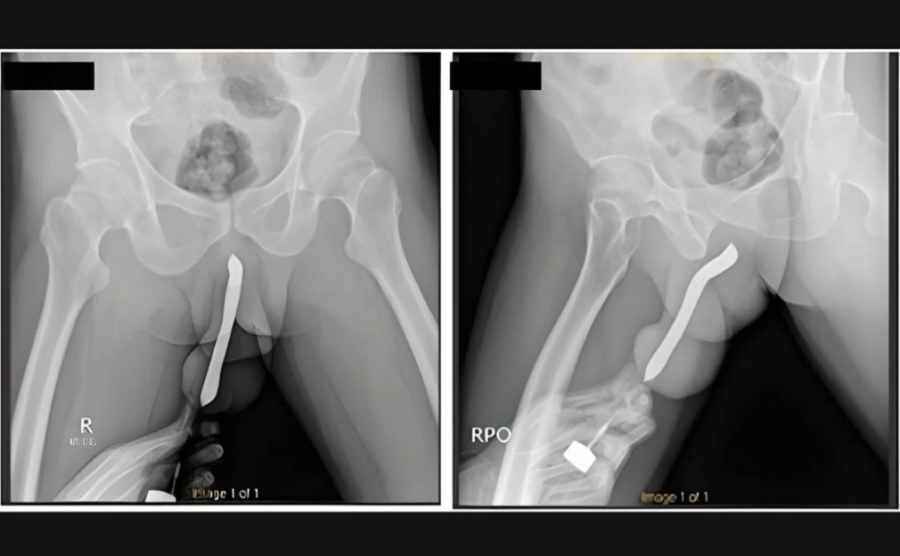

Um homem de 43 anos, da Indonésia, precisou passar por uma cirurgia após uma escova de dentes quebrar dentro do pênis dele durante uma relação sexual. O objeto foi inserido no órgão sexual pelo próprio paciente.

Ele admitiu para os socorristas que enfiou a escova de dentes no órgão sexual para “satisfação pessoal”. Também acrescentou que já havia feito um pequeno corte no órgão para conseguir inserir objetos no local com mais facilidade.

O indonésio passou por uma cirurgia de duas horas e recebeu alta três dias depois. Na consulta de retorno, um mês depois, ele disse não ter sofrido complicações e conseguir urinar normalmente. O pênis também voltou ao formato original.